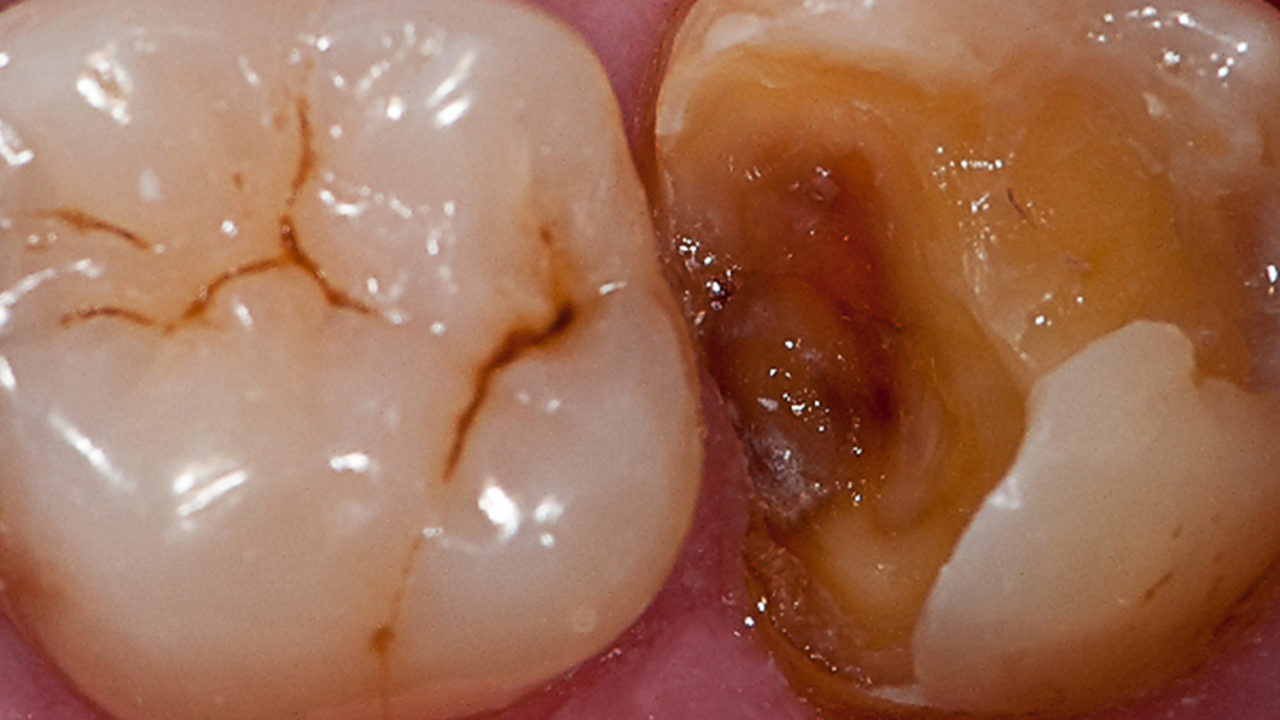

Clinical challenge with advanced layering

Case: Initial case showing defective and leaking old amalgam restorations.